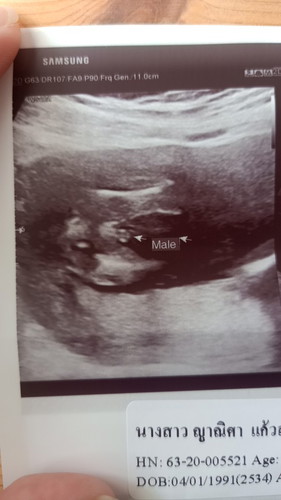

คุณหมอบอกว่าไม่ชัวร์ น่าจะเป็นชาย 90% รบกวนแม่ๆ และผู้รู้ ช่วยฟันธงหน่อยคร้า

Male = ผู้ชายค่ะ น่าจะชัวร์นะคะแม่

หมอบอกแล้วว่าชาย เชื่อหมอนะคะ